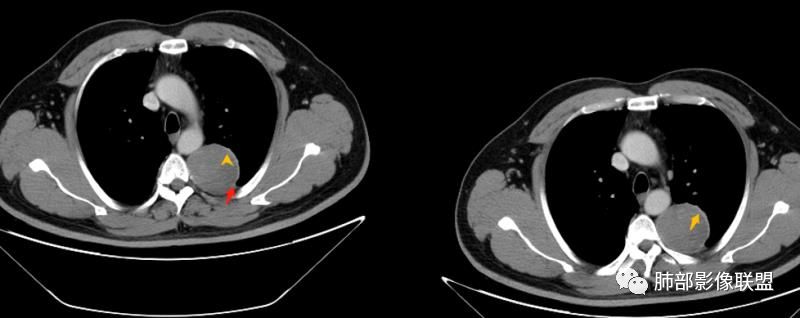

平安是福:平扫31Hu,动脉期33–42Hu,静脉期,39–54Hu。

1.左上胸内脊柱旁半圆形肿块,质地坚实,密度比较均匀。

2.病灶周边见胸膜掀起,应当考虑胸壁或是纵隔来源,肺内病变不会如此。

3.降主动脉这一相对固定结构向前方推移,提示病灶相对坚实且有牢固附着点,不支持来自柔软的肺组织。

4.可疑肋间动脉病供血,提示肿块来自后纵隔的可能性。

7.静脉期轻度强化,注意不是环形强化,亦未显示明确的“AB区”,神经鞘瘤与副节瘤亦未找到支持点。

综上,病灶定位胸壁或后纵隔,就发病率而言,神经源性可能性较大。